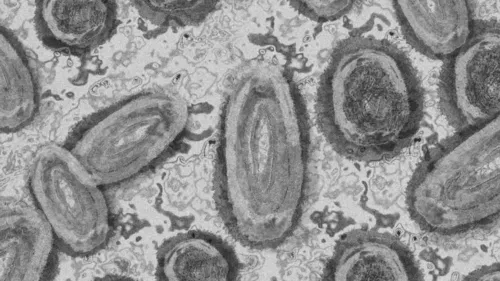

Autor De acordo com secretaria estadual da Saúde, já são 145 casos de varíola dos macacos confirmados em SP - Foto: Pixabay

Pacientes infectados pela varíola dos macacos e moradores de São Paulo têm relatado dificuldades ao diagnosticar a doença e informações desencontradas pela própria equipe médica que os atendeu. Como publicado pelo Estadão, a doença tem seguido por aqui um padrão já observado em outros países e atingido principalmente homens gays e bissexuais da capital. Três deles foram ouvidos pela reportagem e relatam sintomas fortes, dores pelo corpo e feridas que demoram para cicatrizar.